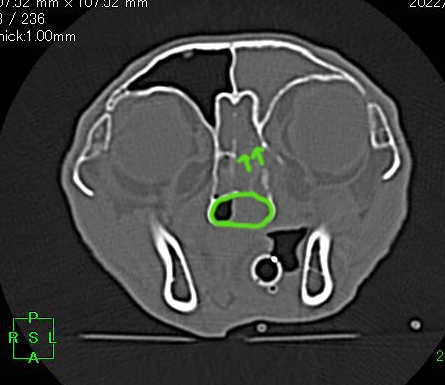

CT検査所見↓

鼻の中に腫瘍性病変(緑の円)と脳との壁である篩板(しばん)が破壊されている所見(矢印)がみられます。